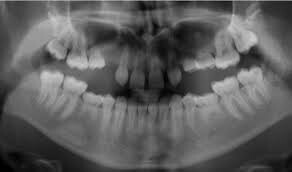

Your dental professional will be able to tell if you have any missing teeth. Usually, they will need an x-ray to confirm this. Gaps between your teeth, losing a baby tooth with no adult tooth taking its place or having a baby tooth longer than normal are all signs of having congenitally missing teeth.